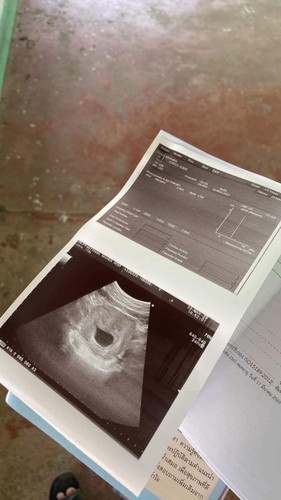

รูปนี้คือ9wคะเเม่ถ้า10wน่าจะเจอน้องเเล้วค่ะ เเต่ยังไงก็ขอให้เเม่เจอตัวเล็กหน๊าเป็นกำลังใจให้ค่ะ

10week เป็นตัวเห็นติ่งแขนขาแล้วค่ะ ถ้าไม่เจอแบบนี้ น่าจะท้องลมค่ะ